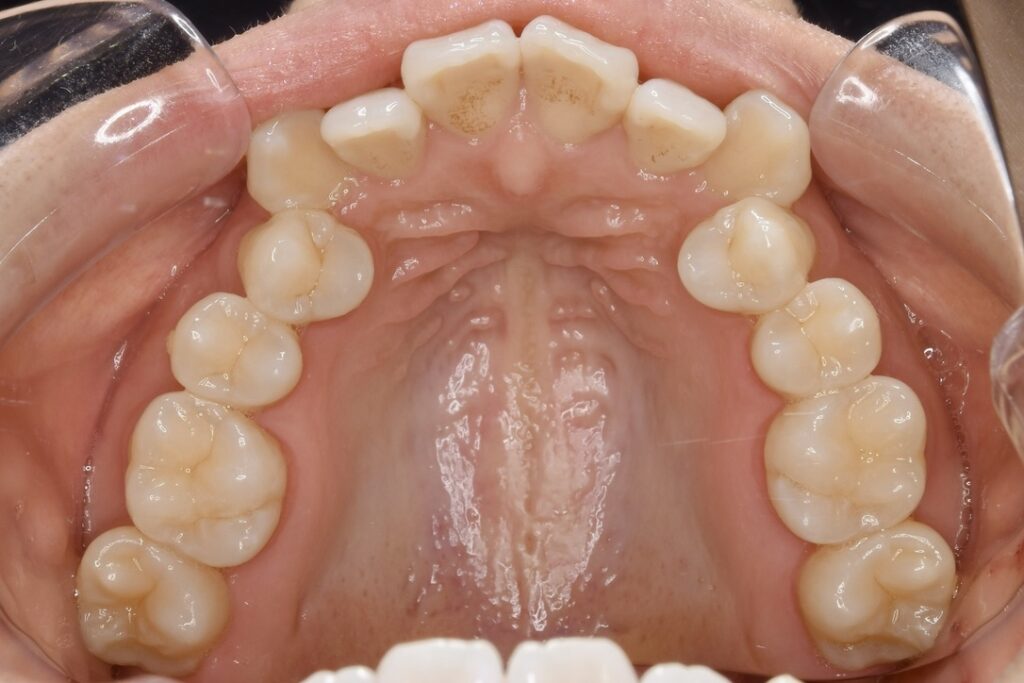

上あご 内側

| 主訴 | 上の歯が前に出ている気がして気になる。 |

|---|---|

| 診断名・主な症状 | 叢生 |

| 年齢 | 23歳 |

| 治療内容 | 上の奥歯を後ろに引くことでできたスペースを利用して前歯のデコボコを解消しました。 |

| 使用装置 | 舌側矯正(ワイヤー) 表側矯正(ワイヤー) 矯正用ミニインプラント |

| 抜歯部位 | 抜歯なし |

| 治療期間 | 1年9ヶ月 |

| 通院回数 | 24回 |

| 費用 | 120万円程度(税別) 231 |

| リスク・副作用 | 痛み、歯肉退縮、歯根吸収、抜歯に伴う出血や腫れが生じることがあります。 |